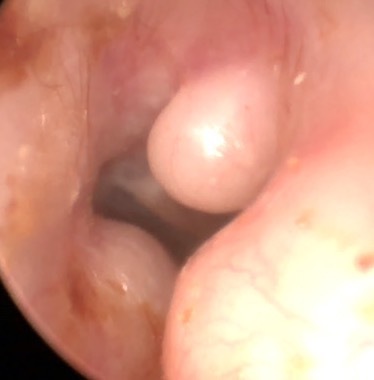

Cholesteatoma Clinical

Atelectasis/Retraction

Tympanic Membrane